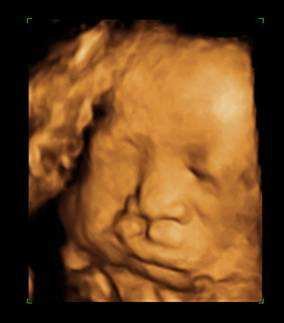

【108-1 醫學(六) 第26題】

26歲孕婦,G5P3A1,妊娠32週,接受超⾳波檢查,結果如圖所⽰,下列何者為最可能的診斷?

詳解

破題關鍵

這題的解題核心在於仔細觀察胎兒的臉部超音波影像,圖片中胎兒的上唇有明顯的裂開缺損,這是典型的唇裂(cleft lip)表現。

選項拆解